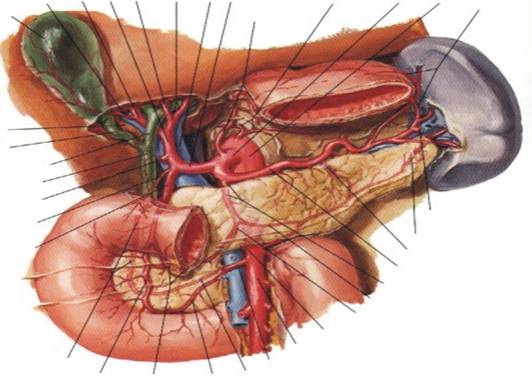

a.hepatica

proprie vena

porta (aici

cu origine prin trunchi comun)

a.hepatica dreapta a.hepatica comuna aorta

abdominala

a.cistica trunchi

celiac aa.gastrice scurte

vezicula biliara a.gastrica stanga

triunghi cistico-

hepatic (Calot)

canal cistic

canal hepatic comun

CBP

a.gastrica dreapta a.gastroepiploica stanga

a.supraduodenala

a.cozii pancreasului

a.gastroduodenala a.pancreatica mare

a.splenica

a.pancreatica dorsala

a.pancreatica inferioara

ram anastomotic

a.colica medie (sectionata)

artera pancreaticoduodenala AMS

posterosuperioara (ascunsa) a.pancreaticoduodenala inferioara

a.pancreaticoduodenala anterosuperioara a.pancreaticoduodenala posteroinferioara

a.gastroepiploica dreapta a.pancreaticoduodenala anteroinferioara